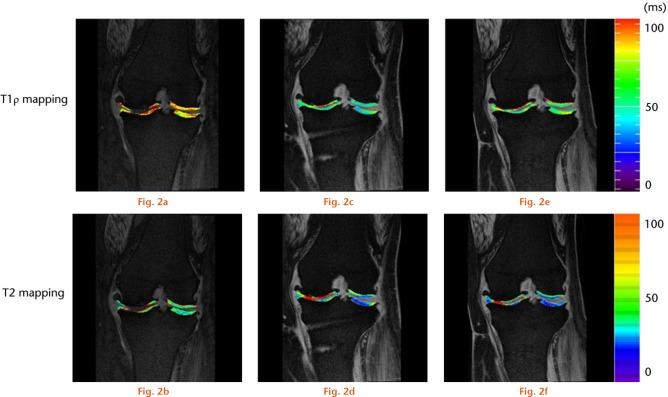

Coronal T1ρ and T2 mapping and three-dimensional gradient-echo images were obtained from 20 subjects with medial knee osteoarthritis. We set the regions of interest (ROIs) on the full-thickness cartilage of the medial femoral condyle (MFC) and medial tibial plateau (MTP) of the knee and measured the cartilage thickness (mm) and T1ρ and T2 relaxation times (ms). Statistical analysis of time-dependent changes in the cartilage thickness and the T1ρ and T2 relaxation times was performed using one-way analysis of variance, and Scheffe's test was employed for post hoc multiple comparison.

The cartilage-like repair tissue appeared on the cartilage surface of the medial compartment post-operatively, and the cartilage thickness showed a significant increase between the pre-operative and one-year post-operative time points (MFC; p = 0.003, MTP; p < 0.001). The T1ρ values of the cartilage-like repair tissue showed no difference over time, however, the T2 values showed a significant decrease between the pre-operative and one-year post-operative time points (MFC; p = 0.004, MTP; p = 0.040).

This study clarified that the fibrocartilage-like repair tissue appeared on the articular surface of the medial compartment after HCO as evidenced by MRI T1ρ and T2 mapping.Cite this article: H. Nishioka, E. Nakamura, J. Hirose, N. Okamoto, S. Yamabe, H. Mizuta. MRI T1ρ and T2 mapping for the assessment of articular cartilage changes in patients with medial knee osteoarthritis after hemicallotasis osteotomy. Bone Joint Res 2016;5:294-300. DOI: 10.1302/2046-3758.57.BJR-2016-0057.R1.